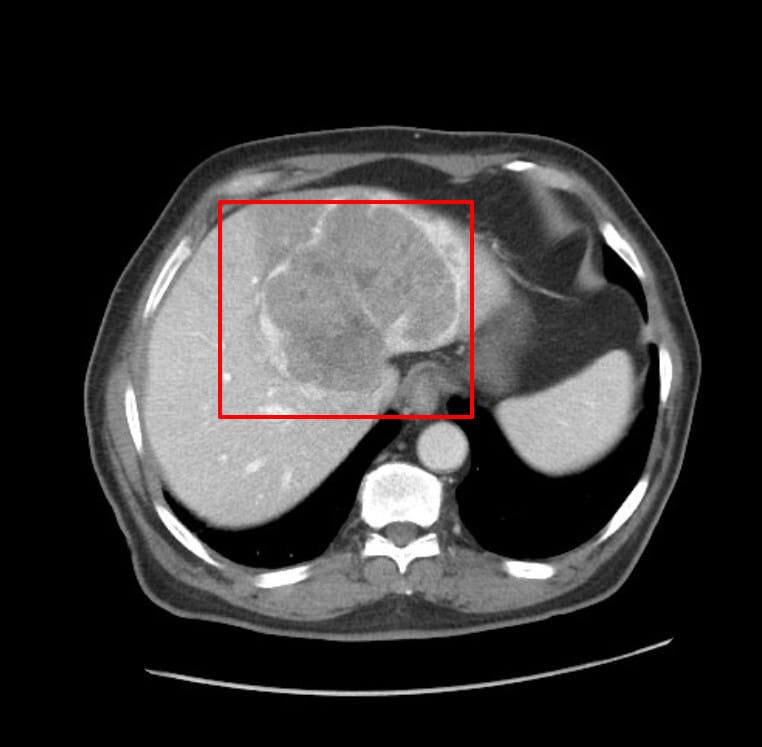

| 문맥기(Portal venous phase) |

| – 병변이 조영이 감소하여 상대적으로 음영이 떨어짐(washout) |

| – 주변 간실질은 조영제가 남아 있어 병변이 더 어둡게 보임 |

| – 간세포암의 전형적인 washout 소견 |

| 지연기(Delayed phase) |

| – washout 현상 지속 |

| – 병변이 더욱 더 저음영(hypodense) 으로 보임 |

| – 일부 경우에는 주변 섬유성 피막(capsule) 이 조영되어 외곽 고리처럼 보일 수 있음 |

Arterial – Portal

Jamouz R, Hepatocellular carcinoma. Case study, Radiopaedia.org (Accessed on 21 Apr 2025) https://doi.org/10.53347/rID-72735